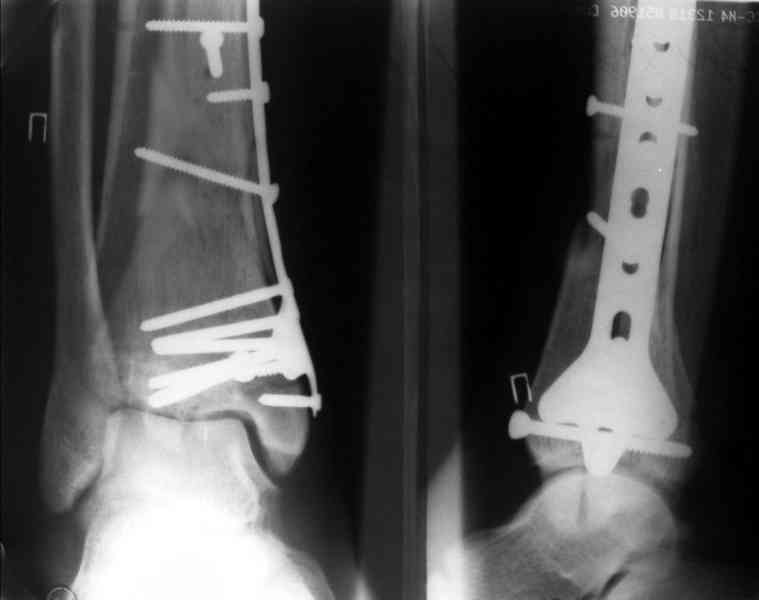

На рентгенограммах типичный перелом пилона по типу С-3. есть опыт до 100 открытых опреаций у нас в клинике. 20 примерно в год. Принцип один -все внутрисуставные переломы нуждаются в открытой репозиции и внутренней стабильной фиксации. При поступлении КТ не надо, так как получается только нагромождение костей. Истинной картины нет. Главное восстановить длину малоберцовой кости - это ключ к успеху. При поступлении меньше всего надо думать о сосудистых расстройствах, т.к. сама операция и репозиция даже сначала частичная даёт улучшение сосудитых нарушений. Причём очень быстро. Операция в 2этапа. При поступлении доступ позади наружной лодыжки, причём обязательно. После этого репозиция малоберцовой кости и фиксация пластиной 1/3 трубки под винт 3,5. Дренаж и любой аппарат наружной фиксации. Затем после спадения отёка на 5-7-10 день аппрат снимается и дугообразный разрез спереди от медиальной лодыжки 10-12 см. Главной чтобы расстояние между 1 и вторым разрезом было не меньше 7-8 см. Тогда не будет некрозов лоскутов. Таранная кость используется как матрица на неё укладываются отломки и фиксируются пицами. Ренг-контроль. Отломки лежат все отдельно, но ничего не высыпется. При переломах С-3 всегда нужна костная пластика (из крыла). Фиксация пластиной лист клевера простой или LCP. Гипс не нужен. Дренаж до 48 часов. Операция длится 3-4 часа обязательно без жгута. Посылаю примерно такой же случай.

Послала ещё два снимка, если не пройдут, пошлю ещё. Дрягин. Если есть вопросы, готов ответить.